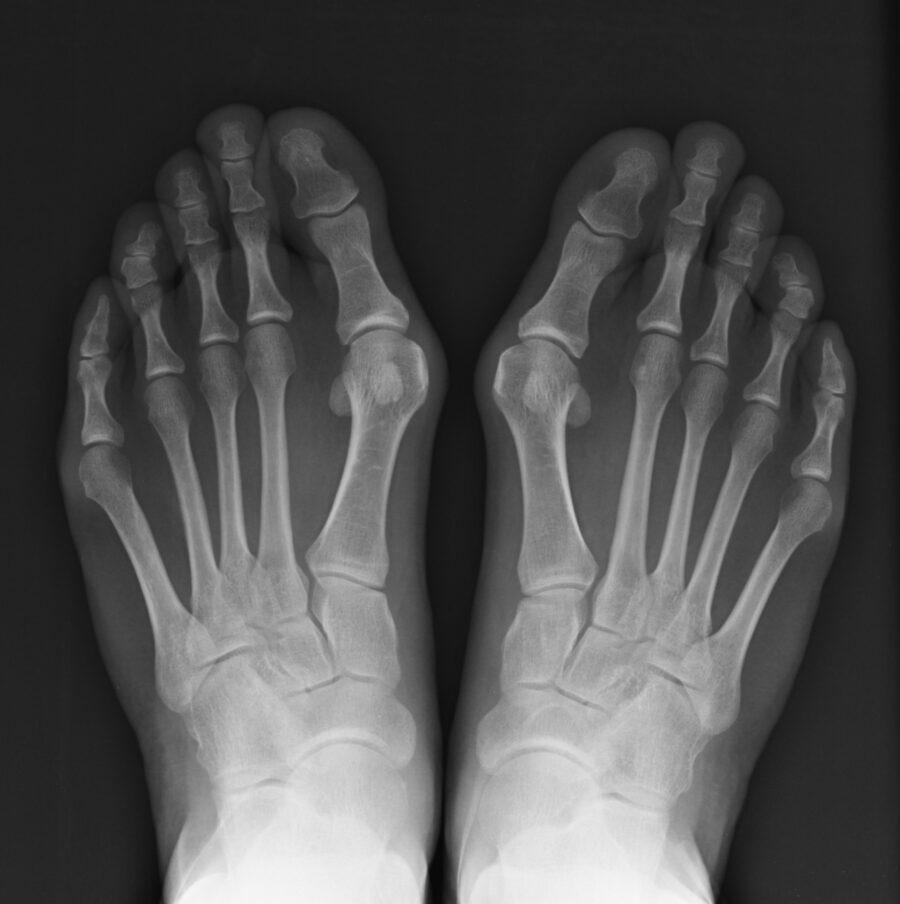

L’alluce valgo si presenta come una deformità del primo dito del piede (l’alluce appunto) che tende a deviare verso l’esterno, anziché proseguire in linea retta. Questa deformazione determina una lussazione delle piccole ossa che ospitano l’articolazione del dito alluce. Tale fenomeno è spesso accompagnato alla “cipolla”, un’infiammazione della parte interna del piede che si forma per via dello sfregamento contro la calzatura.

Il rimedio al problema arriva ancora una volta dall’intervento chirurgico, che va ad agire sulle ossa dei piedi oppure sulle parti molli. Si dovrà comunque procedere all’intervento chirurgico SOLO DOPO il parere di uno specialista e a seguito di valutazioni radiografiche del piede in stato di carico, così da valutare la precisa deviazione del dito alluce.